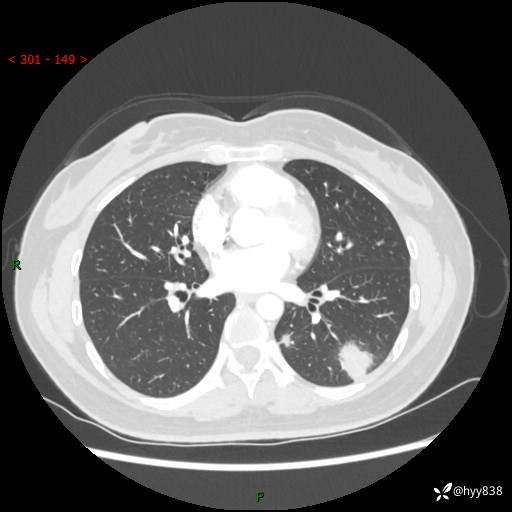

【患者信息】:36岁/女

【主诉】:左侧下胸部阵发性疼痛2周,乏力1周

【现病史及既往史】:患者自诉2周前饮酒后出现左侧下胸部阵发性疼痛,不随呼吸改变,无咳嗽咳痰、头晕头痛、咳血、呼吸困难等不适,于当地第一人民医院查胸部CT提示肺部感染,随后前往我院门诊给予抗感染(左氧氟沙星)治疗1周,自诉胸痛较前好转,感乏力、头晕,偶尔干咳,无咳痰,无发热、畏寒、胸闷、咯血、四肢酸痛、腹泻、腹痛等不适,门诊复查胸部CT提示:左肺下叶感染,病灶较前增加增大,遂以“肺部感染”收入我科。 起病以来,患者精神、饮食、睡眠可,大小便正常,体力体重无明显变化。

【检查】:胸部CT增强(外院平扫)